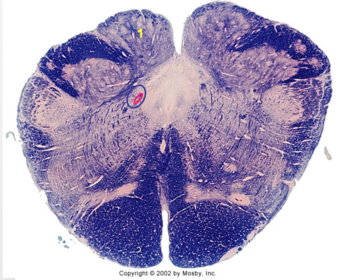

| Nucleus gracilis | |

| Accessory nucleus | |

| Medial longitudinal faciculus | |

| Pyramidal decussation | |

| Medullary pyramids | |

| Anterior spinocerebellar tract | |

| ALS | |

| Posterior spinocerebellar tract | |

| Spinal tract of V | |

| Spinal nucleus of V | |

| Nucleus cuneatus | |

| Fasciculus cuneatus | |

| Fasciculus gracilis | |

| Central canal | |

| Internal acruate fibers | |

| Lateral (external/accessory) cuneate nucleus | |